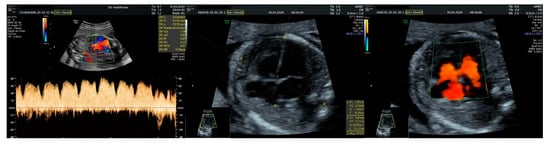

- an isolated aortic arch anomaly (supposedly aneurysmal dilation from which the left common carotid artery emerges) and coarctation of the aorta with the anterograde flow;

- ventricular septal defect, coarctation of the aorta, and a vascular formation located superior from the aortic arch with the appearance of an arteriovenous fistula;

- aneurysmal dilation located above the pulmonary trunk bifurcation and a dilated left common carotid artery with a retrograde flow;

- minor ventricular septal defect with a normal ductus venosus triphasic flow.